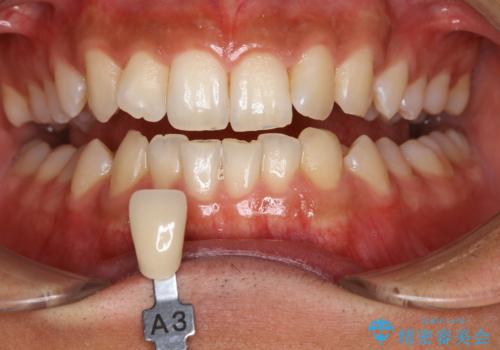

- 歯を白くしたいとのことでした。

オフィスホワイトニング(TION Whitening・処置前クリーニング込み)コースを行いました。

処置後は艶のある綺麗な白さになりました。

ご希望の自然な白さに、トーンアップしたとのことで満足していただけました。